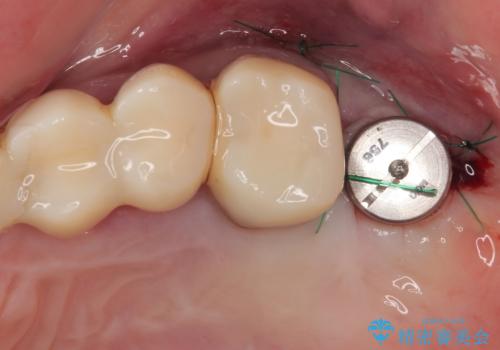

かかりつけ医では、歯周病治療は終了したため、抜歯を行った右上奥歯にインプラント埋入を行うとの案内があったそうです。

インプラント治療の注意事項(リスク・副作用など)

- 外科手術のため、術後に痛みや腫れ、違和感を伴います

- メンテナンスを怠ったり喫煙により、お口の中に大きな悪影響を及ぼすインプラント周囲炎等にかかる可能性があります